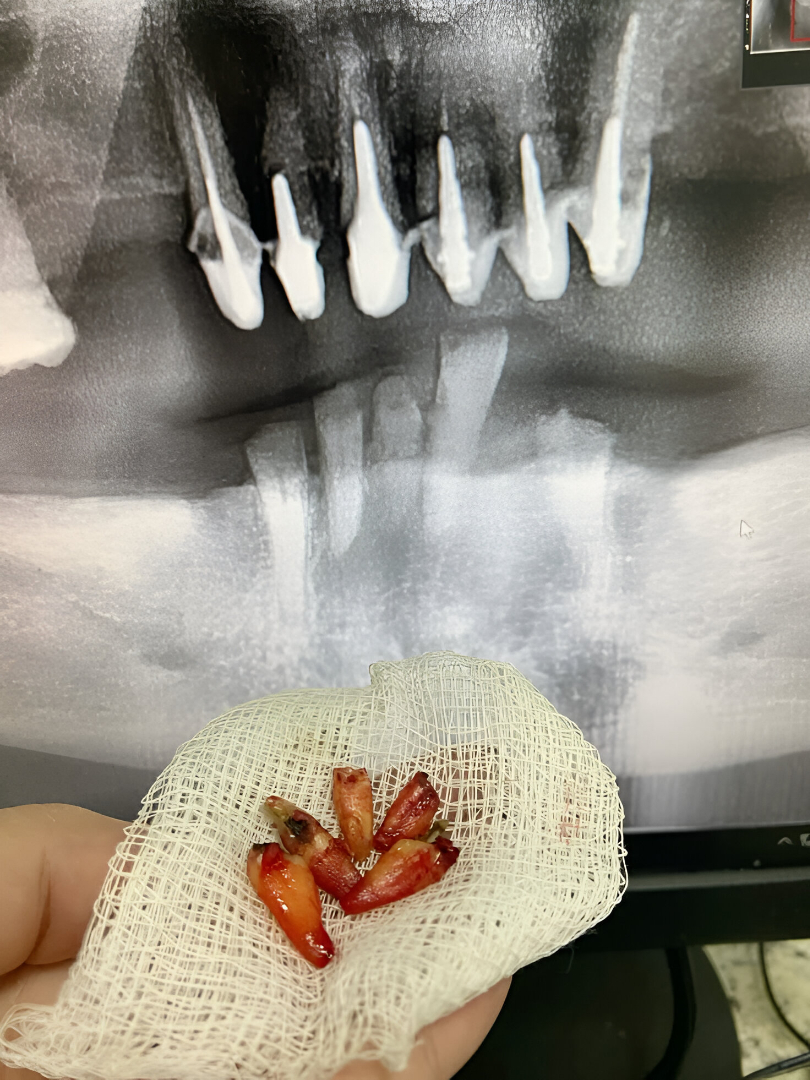

Oral Surgery

Digital imaging, surgical microscopes